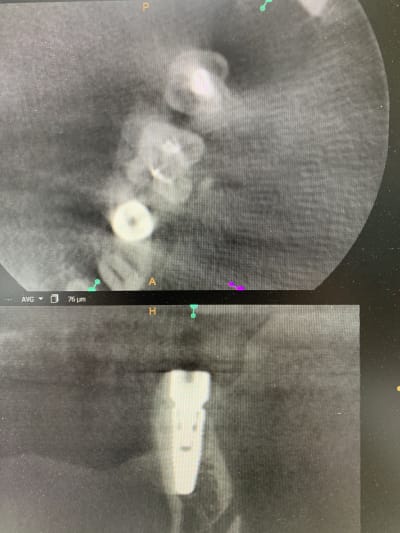

Il y a vraiment des différences de dingue entre les machines !

Les images 3 et 4, les images 6 et 7 sont prises à quelques années d’intervalles.

La machine de 2008 fait très peu d’artefacts, celle de 2018 énormément. Elle à le mar pour les « supprimer », mais ça n’arrange rien !

Les artefacts métalliques sont bien différents selon les machines.

A l’adf on me dit « regardez on voit même les spires des implants », avec ma bécanne de 2008 je vois les spires des vis dans les implants, les têtes de vis... je n’ai rien vu d’équivalent sur les machines récentes.

Regardez comme les tenons sont bien trop larges à la radio !

Les implants sont de gros pâtés blancs...